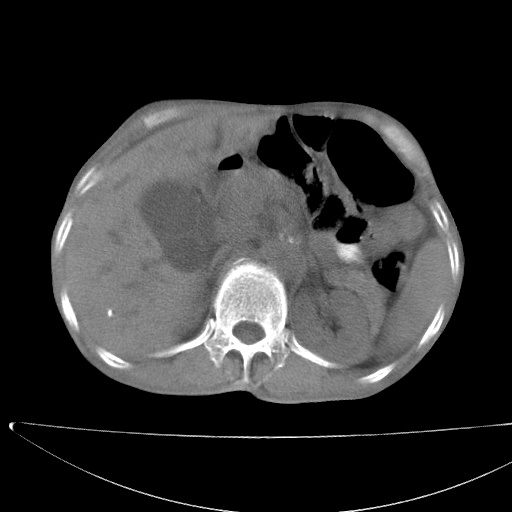

标题: CT17147:男70岁,上腹部不适1月。 [打印本页]

患者男70岁,上腹部不适1月。8年前有胃癌手术史。余病史不祥。

1)胃癌术后,不排除复发可能。2)考虑肝脏及腹膜后淋巴结转移瘤。3)肝内胆管扩张,胆囊增大。4)肝内胆管结石(或钙化)。5)脾脏钙化灶。6)腹水。7)右侧少量胸腔积液。

建议:行ct增强扫描检查。

1、胃癌根治胃空肠吻合术后,残胃癌?

2、肝门区占位性病变并胆道上段梗阻(肝内胆管扩张、胆囊增大),考虑肝门区淋巴结转移累及胆总管,建议ct增强扫描;

3、右侧胸腔少量积液、少量腹水;

4、肝右叶胆管结石。